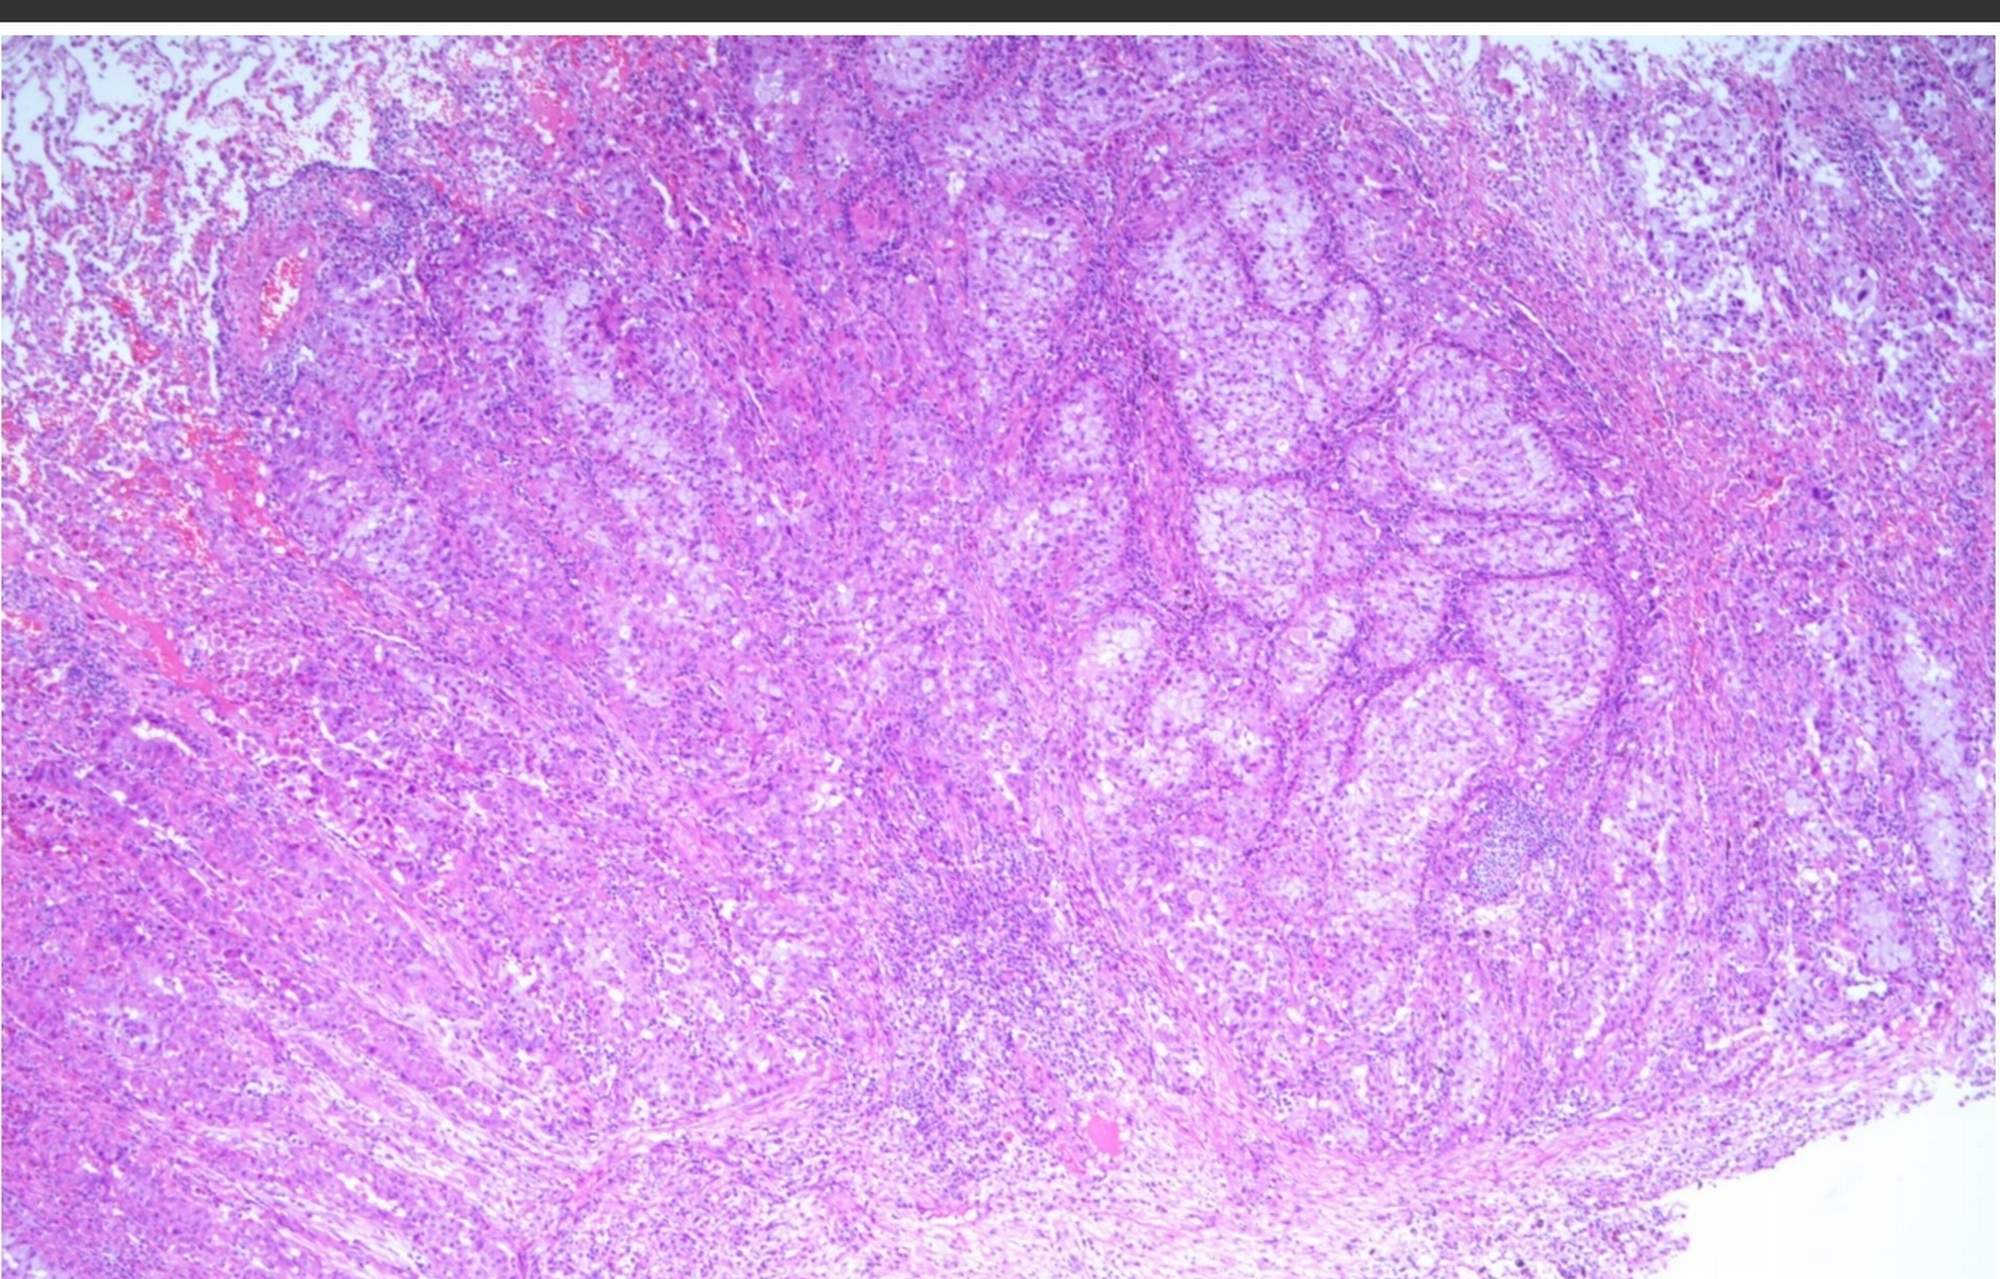

术前检查无手术禁忌,行单孔胸腔镜左下肺切除,术中冰冻病理提示左下肺浸润型腺癌,行肺癌根治清扫纵隔淋巴结,术后病理纵隔淋巴结未见转移。术后第2天拔除胸管,术后3天出院,这周来门诊复查肺膨胀好,患者无不适主诉。术后病理诊断pT1bN0M0 IA2期,不需要术后辅助治疗,只需定期随访复查。

图3:术后10天胸片

患者在我的建议下接受手术治疗。行单孔胸腔镜右下肺叶切除,术中冰冻病理提示右下肺浸润型腺癌,行肺癌根治清扫纵隔淋巴结,术后病理纵隔淋巴结未见转移。术后恢复顺利,术后3天出院,这周来门诊复,诉有轻微的咳嗽及胸痛,可以耐受。还遇到了上面那位左下肺肺癌患者,还互相加了微信,互相鼓励,一起走在抗癌的道路上。复查胸片肺膨胀好。术后病理右下肺浸润性腺癌伴坏死,实性型约占50%、腺泡型约占50%,肿物最大径约6cm,,术后病理诊断pT3N0M0 IIB期。按照NCCN指南患者需要术后辅助治疗,行基因检测,如果发现EGFR敏感基因突变,可行奥希替尼辅助靶向治疗。如果无基因突变,建议以铂类为基础的方案进行辅助化疗。

图9:术后1周胸片